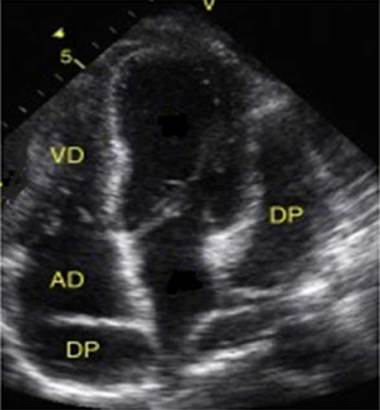

On the third day of hospital stay, HIV, VDRL, and culture test results were negative, and other causes of fever, including an autoimmune origin, were considered. Anti-nuclear antibodies, extractable antibodies, and anti-DNA antibodies, as well as an aprocalcitonin test, were requested as part of the care protocol in patients with fever of unknown origin. A possible endocardial infection focus was also considered, so a transthoracic echocardiogram was requested, the results of which were obtained the next day and revealed mild pericardial effusion located in the posterior wall of the right atrium, moderate pericardial effusion adjacent to left cavities (Figure 2), and no signs of tamponade, constriction, or hemodynamic effects.

Transthoracic echocardiogram showing mild pericardial effusion in the posterior wall of the right atrium and moderate adjacent pericardial effusion adjacent to the left cavities. AD: right atrium; RV: right ventricle; PD: pericardial effusion.

Figure 2: Transthoracic echocardiogram showing mild pericardial effusion in the posterior wall of the right atrium and moderate adjacent pericardial effusion adjacent to the left cavities. AD: right atrium; RV: right ventricle; PD: pericardial effusion.

Source: Document obtained during the study.